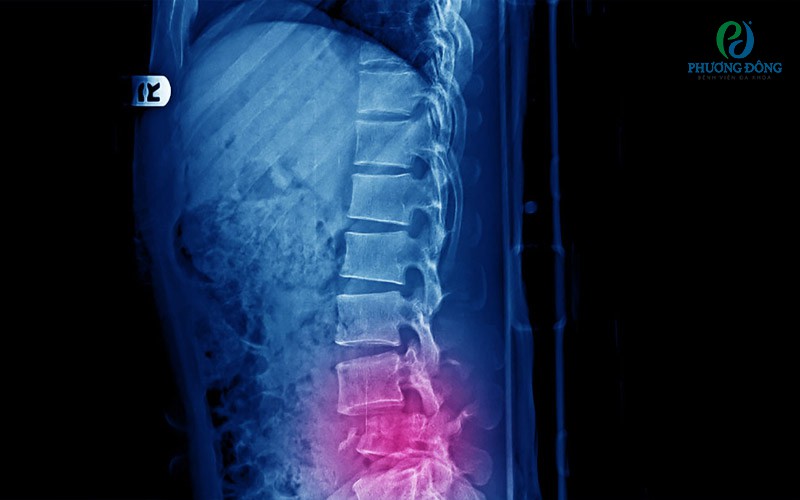

Hình ảnh chụp X-quang của người bệnh Hình ảnh chụp X-quang của người bệnh

• Chụp X-quang hoặc CT Scan cột sống thắt lưng: Nhằm khảo sát cấu trúc xương, phát hiện gãy xương, thoái hóa, gai xương hoặc bất thường giải phẫu.